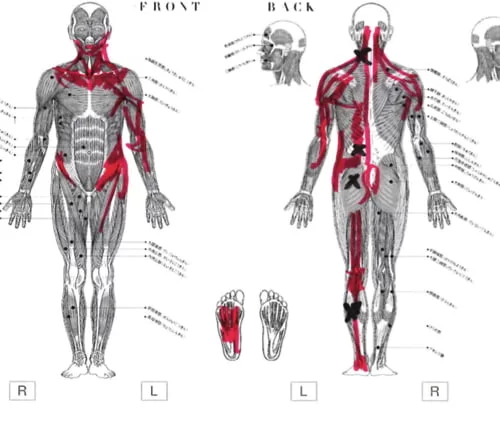

痛みの場所はここ。

そして脚の前側にも痛み

膝下のここにも痛み。

そして足先はシビレがある状態でした。

こんな感じで筋肉や腱の硬直やヨジレがありました。

今回のお客様はちょうどこんな感じで背中と太腿の筋肉が硬直していて

腰を上からも下からも引っ張っている状態。

痛みの主な原因はこの硬直によって骨盤が引っ張られてヨジレが生まれ

ヨジレた筋肉などが神経に当たって痛い。

動いた際に違和感を感じる部分はここと

ふくらはぎ。

そして足裏。

お身体の状態を診させて頂くとこんな感じでした。

またお仕事などで硬直が進んでいましたが